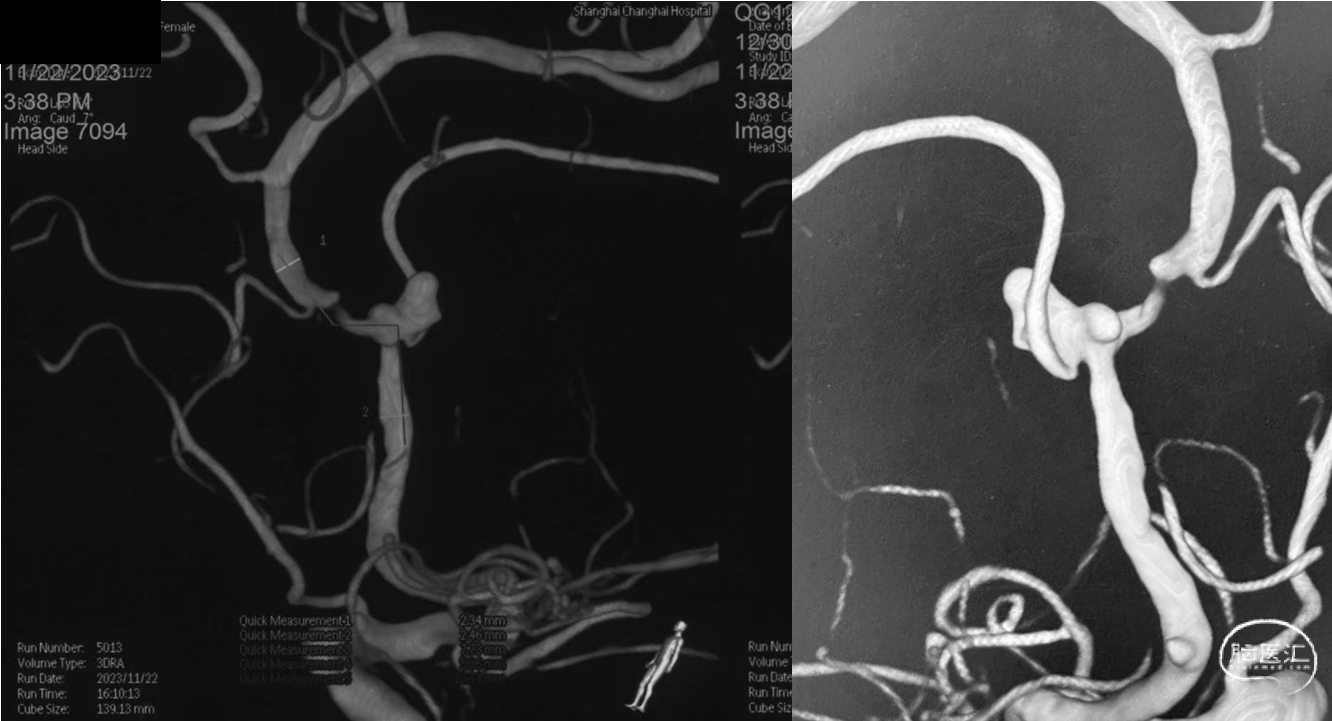

本例患者是左侧大脑前动脉A2段动脉瘤,形态不规则,合并载瘤动脉狭窄,采用血流导向装置植入治疗后获得较好的影像学结果。